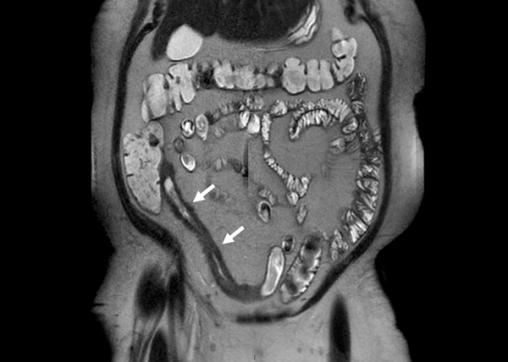

Coupe coronale d'entéro-IRM montrant une sténose iléale (flèches) de maladie de Crohn caractérisée par un épaississement de la paroi iléale et un rétrécissement de la lumière iléale.